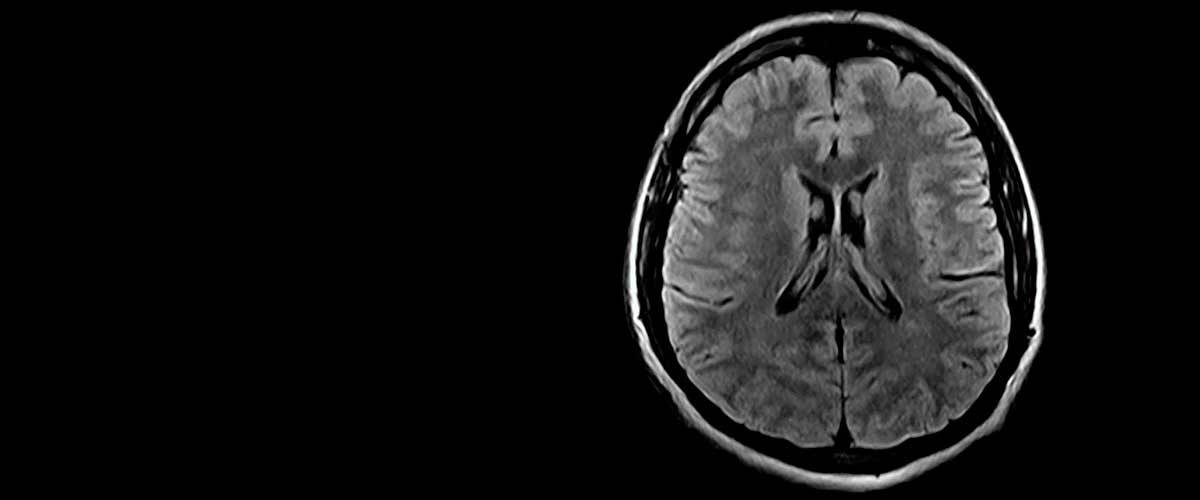

Contamos con equipos de resonancia magnética musculo-esquelética capaces de realizar exámenes con descarga de peso o bipedestación.

En nuestros centros se realizan estudios y diagnósticos de resonancia magnética musculo-esquelética